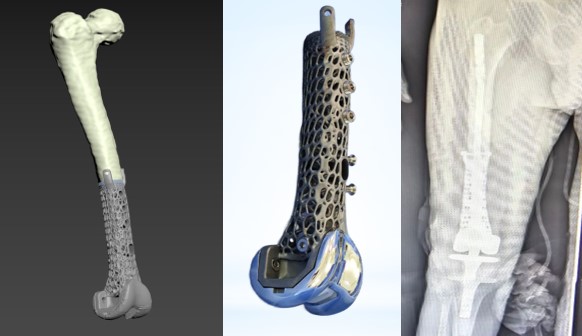

МОЖЛИВОСТІ АДДИТИВНИХ ТЕХНОЛОГІЙ В ОНКОПРОТЕЗУВАННІ КОЛІННОГО СУГЛОБУ

Етапи проектування імплантатів при онкопротезуванні

Пацієнт Г-й І.С.64 роки, остеосаркома стегнової кістки

Проектування та виготовлення індивідуальних аугментів для заміщення дефектів суглобів: М, 48 р, асептична нестабільність онкологічного ендопротеза. Заміщення дефекту індивідуальним аугментом та ревізійним ендопротезом , фіксація БІС, ПММА

Етапи онкологічного протезування